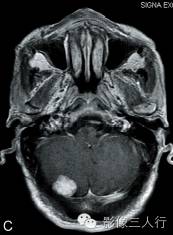

A.T2WI横断面;B.T1WI横断面;C、D、E.增强横断面、矢状面、冠状面;F.HE×100

图A、B:平扫MRI显示右侧小脑后缘类圆形结节状病灶,大小约1.4cm×2.0cm×1.8cm,在T2WI呈稍高信号,T1WI为稍低信号,边界清楚,信号均匀,局部脑组织受压内移。图C~E:Gd-DTPA增强扫描显示结节呈较均匀明显强化,病灶边缘清楚,其中在横轴位图像显示肿瘤中央部分强化较周围明显,且类似日光放射状。矢状位、冠状位图像见肿块强化变均匀一致,紧贴小脑后方硬脑膜或颅骨,但未见明显硬脑膜尾征。